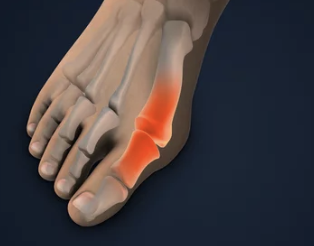

1οΈβ£ μμ§λ°κ°λ½μ΄ νμμ΄μ! π« 무μ§μΈλ°μ¦, λ λꡬλ?

무μ§μΈλ°μ¦μ μμ§λ°κ°λ½μ΄ λ λ²μ§Έ λ°κ°λ½ μͺ½μΌλ‘ νμ΄μ§κ³ , μμ§λ°κ°λ½ κ΄μ μμͺ½μ΄ νμ΄λμ€λ μ§νμ λλ€.

- μμ§λ°κ°λ½ λ³ν: μμ§λ°κ°λ½μ΄ νμ΄μ§λ©΄μ λ° λͺ¨μμ΄ λ³νλκ³ , μ λ°μ μ μ λ λΆνΈν¨κ³Ό ν΅μ¦μ μ λ°ν©λλ€. μ λ μμ μλ νμ΄λμ¨ λΌ λλ¬Έμ μ λ°μ μ μ λλ§λ€ μμ²λ κ³ ν΅μ λκΌμ΅λλ€. π